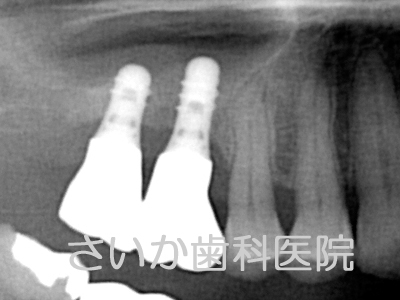

上の奥歯2本を歯周病で失ったため,骨が吸収しています。ヒトの上あご内部には「上顎洞」と呼ばれる空洞があるため,骨の厚みは矢印で示した厚みしかありません(上図右)。

「ソケットリフト」という治療法は「上顎洞」の底面部にインプラントを粘膜を破らないように突きだしてやる方法です。

手術後,しばらくしますと突きだしたインプラント周囲には骨が自然に出来てきます。骨の再生に人工的な物を使用せず,移植も必要としないため,患者様への負担は少ない治療法のひとつです。下の写真はインプラントを入れて5年が経過した写真です(パノラマレントゲンのため,画質が粗くなっています)。